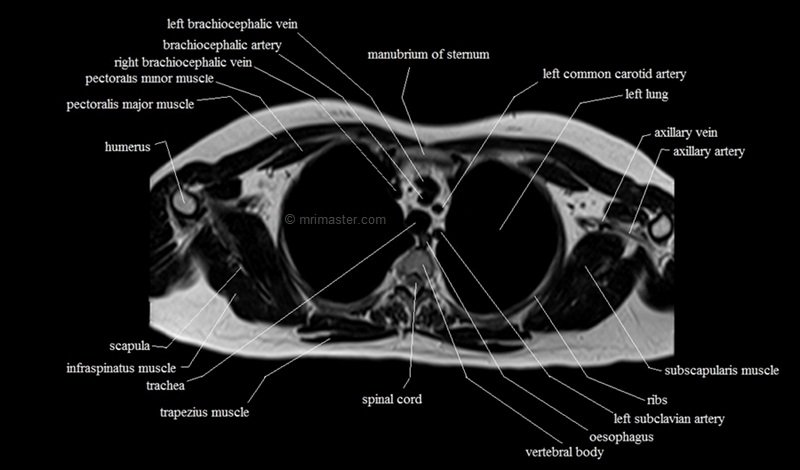

MRI Axial Cross Sectional Anatomy of Chest

This MRI chest (thorax) axial cross sectional anatomy tool is absolutely free to use. Use the mouse scroll wheel to move the images up and down, or alternatively, use the tiny arrows (→) on both sides of the image to navigate through the images. For a more detailed view, double-click the image to view it in full screen, and use the menu in the top right-hand corner to view individual slides or play them in a loop.